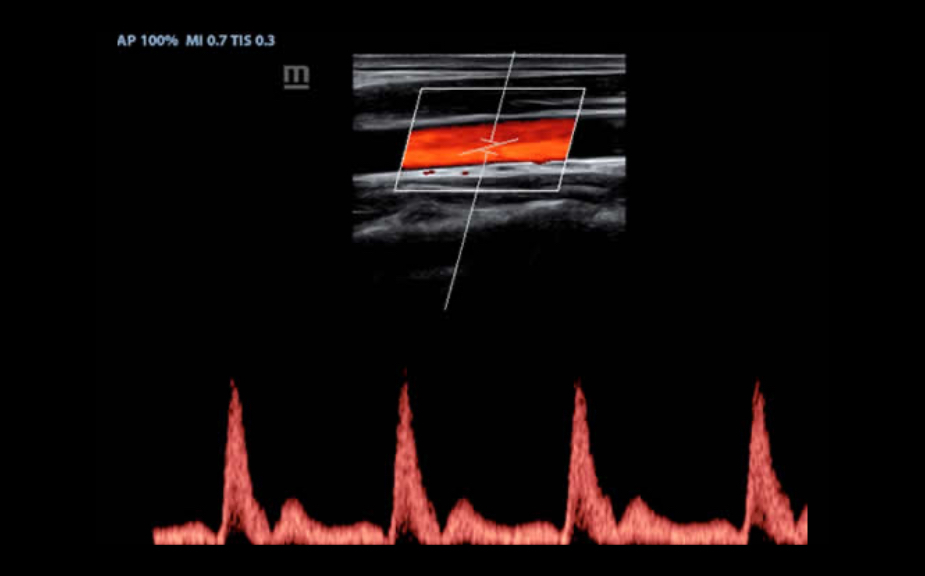

IMT (Intima-Media Thickness)

Automatyczny pomiar grubo?ci kompleksu Intima-Media na przedniej i tylnej ?cianie naczynia, umo?liwia precyzyjn? ocen? stanu t?tnicy szyjnej.